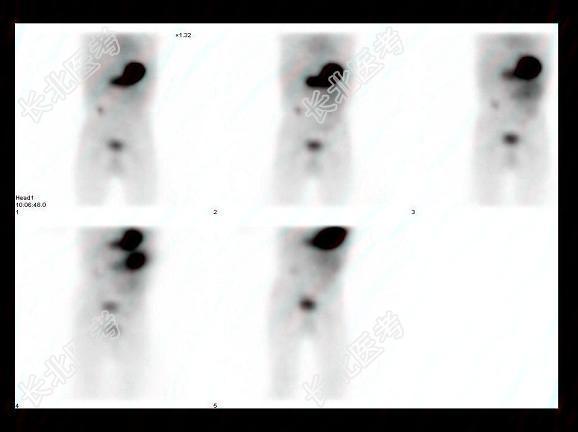

多项选择题2岁男孩,下消化道出血4天, 行TcO腹部显像如图,可能的诊断是 ( )

A、肠重复畸形

B、异位胃粘膜

C、未见异位胃粘膜

D、Barret食管

E、Meckel憩室